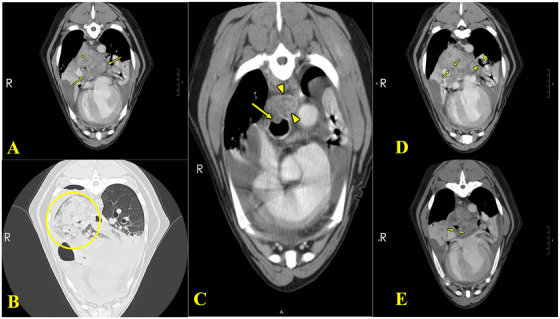

Case presentation: A 5-year-old male neutered Labrador Retriever presented with progressive respiratory distress, leading to pleural effusion and facial swelling. Thoracic radiographs revealed mediastinal mass-like structures and pleural effusion. Computed tomography demonstrated a mediastinal mass-like structure, enlarged tracheobronchial lymph nodes, multifocal narrowing of lobar bronchi and pulmonary veins and compression of the oesophagus and trachea. The dog was humanely euthanized due to poor response to empiric therapy and the owner's perception of suffering. A post-mortem examination confirmed severe chronic mediastinal inflammation with fibrosis and vasculitis consistent with fibrosing mediastinitis.